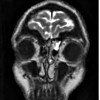

КТ-цистернография

КТ цистернография. Многослойная сканирующая рентгенография спинномозговой жидкости. Проводится после эндолюмбального введения йодсодержащего контрастного материала. Сначала выполняется сканирование вида сбоку, затем необходимое количество фронтальных разрезов. КТ-цистернография является информативной для диагностики посттравматической базальной ликвореи, поскольку позволяет оценить состояние ликвопроводящих путей и ликвородинамики. Кроме того, исследование помогает выявить опухолевые процессы в области мостиково-мозжечкового угла и хиазо-седалищной области, гидроцефалии, аномалии Арнольда-Киари, арахноидальных кист. Стоимость определяется типом и объемом контрастного вещества.